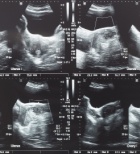

אולטרסאונד רחם

מנסים להרות ולא מצליחים. על בדיקת ב...

פרופ' יגאל וולמן, מומחה לאולטרסאונד במיילדות וגניקול...

14/11/2022